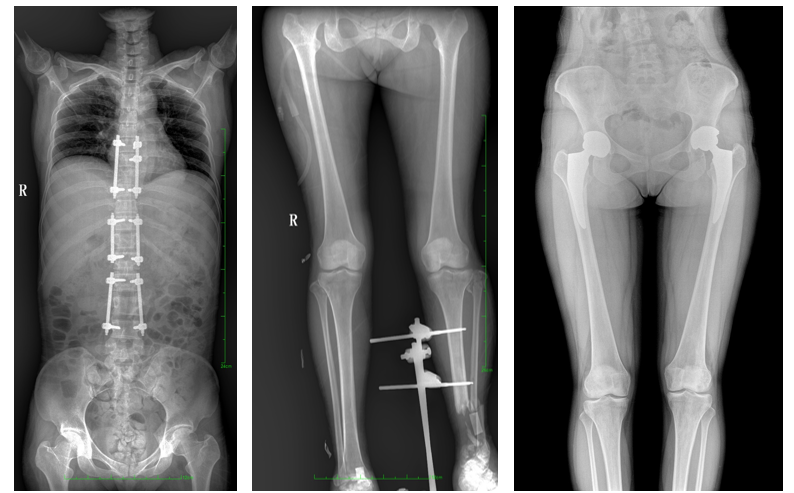

17"*34"有效視野,是市面大尺寸平板的2倍,一次成像不拼接。相較于多張攝影再軟件拼接的DR設備,PLX8600解決了拼接圖像存在密度不均勻,拼接處圖像配準和放大效應等問題,給臨床帶來了真正的大視野影像解決方案,高清畫質(zhì),準確成像不失真,可一次性覆蓋全脊柱或雙下肢影像。PLX8600大視野平板動態(tài)DR攝影速度快,患者可以更快的完成檢查,且單次攝影輻射劑量是常規(guī)多張攝影再軟件拼接DR的1/2或1/3,低劑量給患者更多關(guān)愛。

大視野平板動態(tài)DR全脊柱一次成像